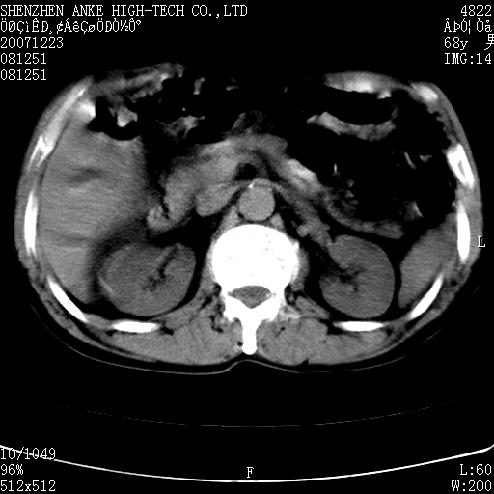

患者:男,63岁,2年前胆囊切除术后,现右上腹部剧烈疼痛近2天.

有无外伤史?右肾包膜下血肿可疑。

主要是问右肾有没有问题?患者无明显外伤史.

未见异常,病人差闭气,伪影较多.

肠道准备不好,干扰影大。

肠道气体伪影干扰太大了,应该是干扰所致,未见明显异常。

肠道准备不好,胃底后壁显示不清,右肾改变考虑为伪影。